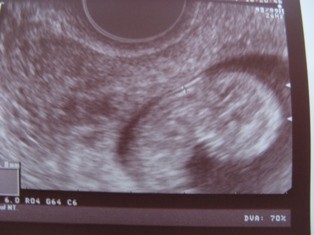

Mi przypomina małego ufoludka:-)